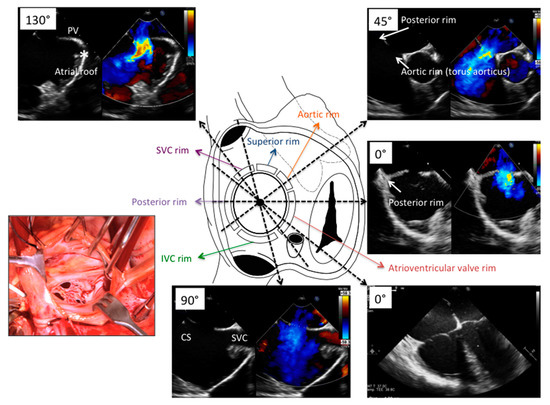

| Basal transverse | SVC, superior aortic, RUPV | Device relationship in atrial roof | 0°, 15°, 30°, 45° | Mid- to upper esophagus |

| Four-chamber | Posterior and AVV rims, maximal ASD diameter | Device relationship to AV valves | 0°, 15°, 30°, | Mid-esophagus |

| Short-axis | Posterior and aortic rims, maximal ASD diameter, PFO tunnel and atrial anterior-posterior distance | Device relationship to AoV and posterior atrial wall | 30°, 45°, 60°, 75° | Mid- to upper esophagus |

| Bicaval | IVC and SVC rims, maximal ASD diameter, PFO amplitude and lenght | Device relationship to RA roof/dome | 90°, 105°, 120° | Mid-to upper esophagus and deep transgastric |

| Long-axis | Dome/roof of LA | Device relationship to LA dome/roof | 120°, 135°, 150° | Mid- to upper esophagus |